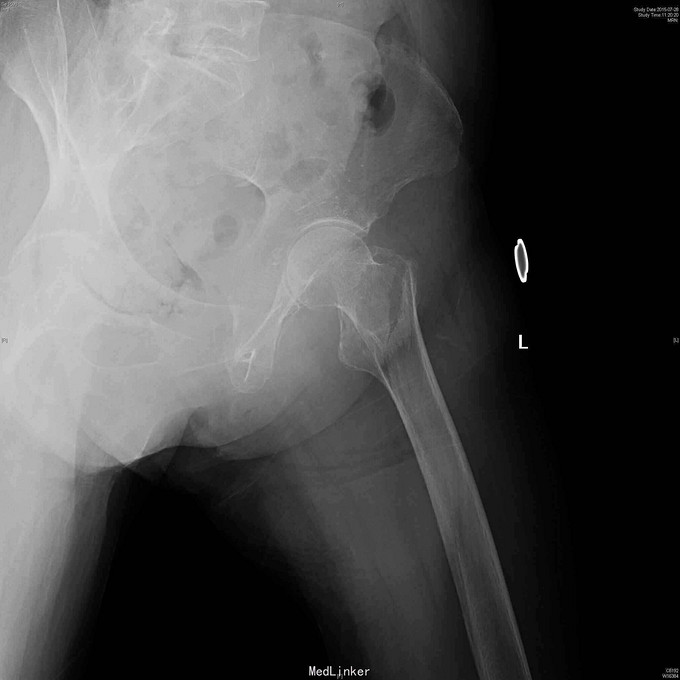

82岁女性,摔倒致左髋疼痛,短缩外旋畸形5小时。

查体:左下肢轻度外旋短缩,左髋大转子叩痛,轴向叩击痛。 左髋放射片:左股骨粗隆间骨折,轻度移位。